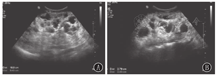

ADPKD是全球发病率最高的单基因遗传性肾病,其发病率为1 /1 000~1 /400,主要是由位于第16号染色体上的PKD1和第4号染色体上的PKD2基因突变引起,有家族史,多于成年后发病,且预后不良,儿童发病少见[10]。ADPKD是一种以器官内囊肿形成为特征的全身性疾病[19],可多器官受累,因此常合并多囊肝、多囊脾、多囊胰等。肾脏的主要病理学改变为肾小管上皮细胞来源的充满液体的囊泡不断形成和扩张,最终与集合管连接不良,尿液排出受阻引起肾小管形成潴留性囊肿,进行性增大,肾脏表面及内部可见大小不等的肉眼可见的囊肿,肾实质残留很少。病变为双侧。患儿年幼时肾脏外形、大小正常或略增大,随着年龄增长,肾内囊肿的大小和数目不断地增大、变多,多数患者40~50岁时肾脏才会出现症状。儿童ADPKD双侧肾脏改变多不典型,超声表现为双肾大小正常或稍大;肾脏的超声表现多数正常或难以断定,肾实质内可见数个囊肿聚集或呈散在分布,囊肿较小、较少,肾实质回声可见;肾盂肾盏均保持正常形态,肾窦未见受压,随着年龄的增长及病情进展,囊肿逐渐增大、增多,囊肿间彼此不相通,囊壁可见成团成簇的强回声点,双肾明显增大,形态失常,表面凹凸不平,肾实质变少(图3)。对于疑似ADPKD患儿,临床应询问家属是否有家族史,综合分析得出诊断。若实际情况需要则应告知患儿要定期复查,随访观察肾内囊肿的发展变化。